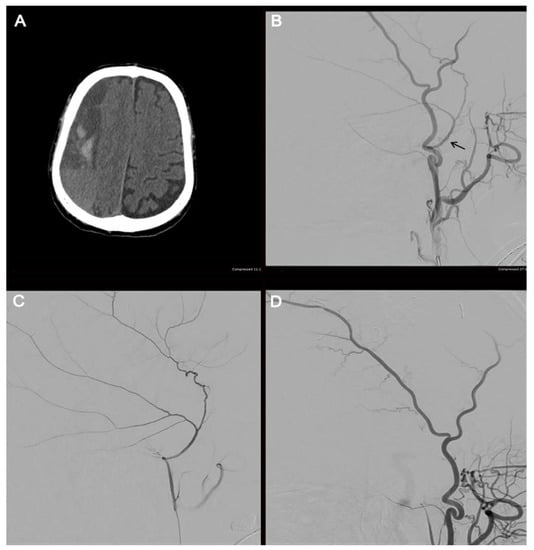

3.2. Grade III: Pseudoaneurysm